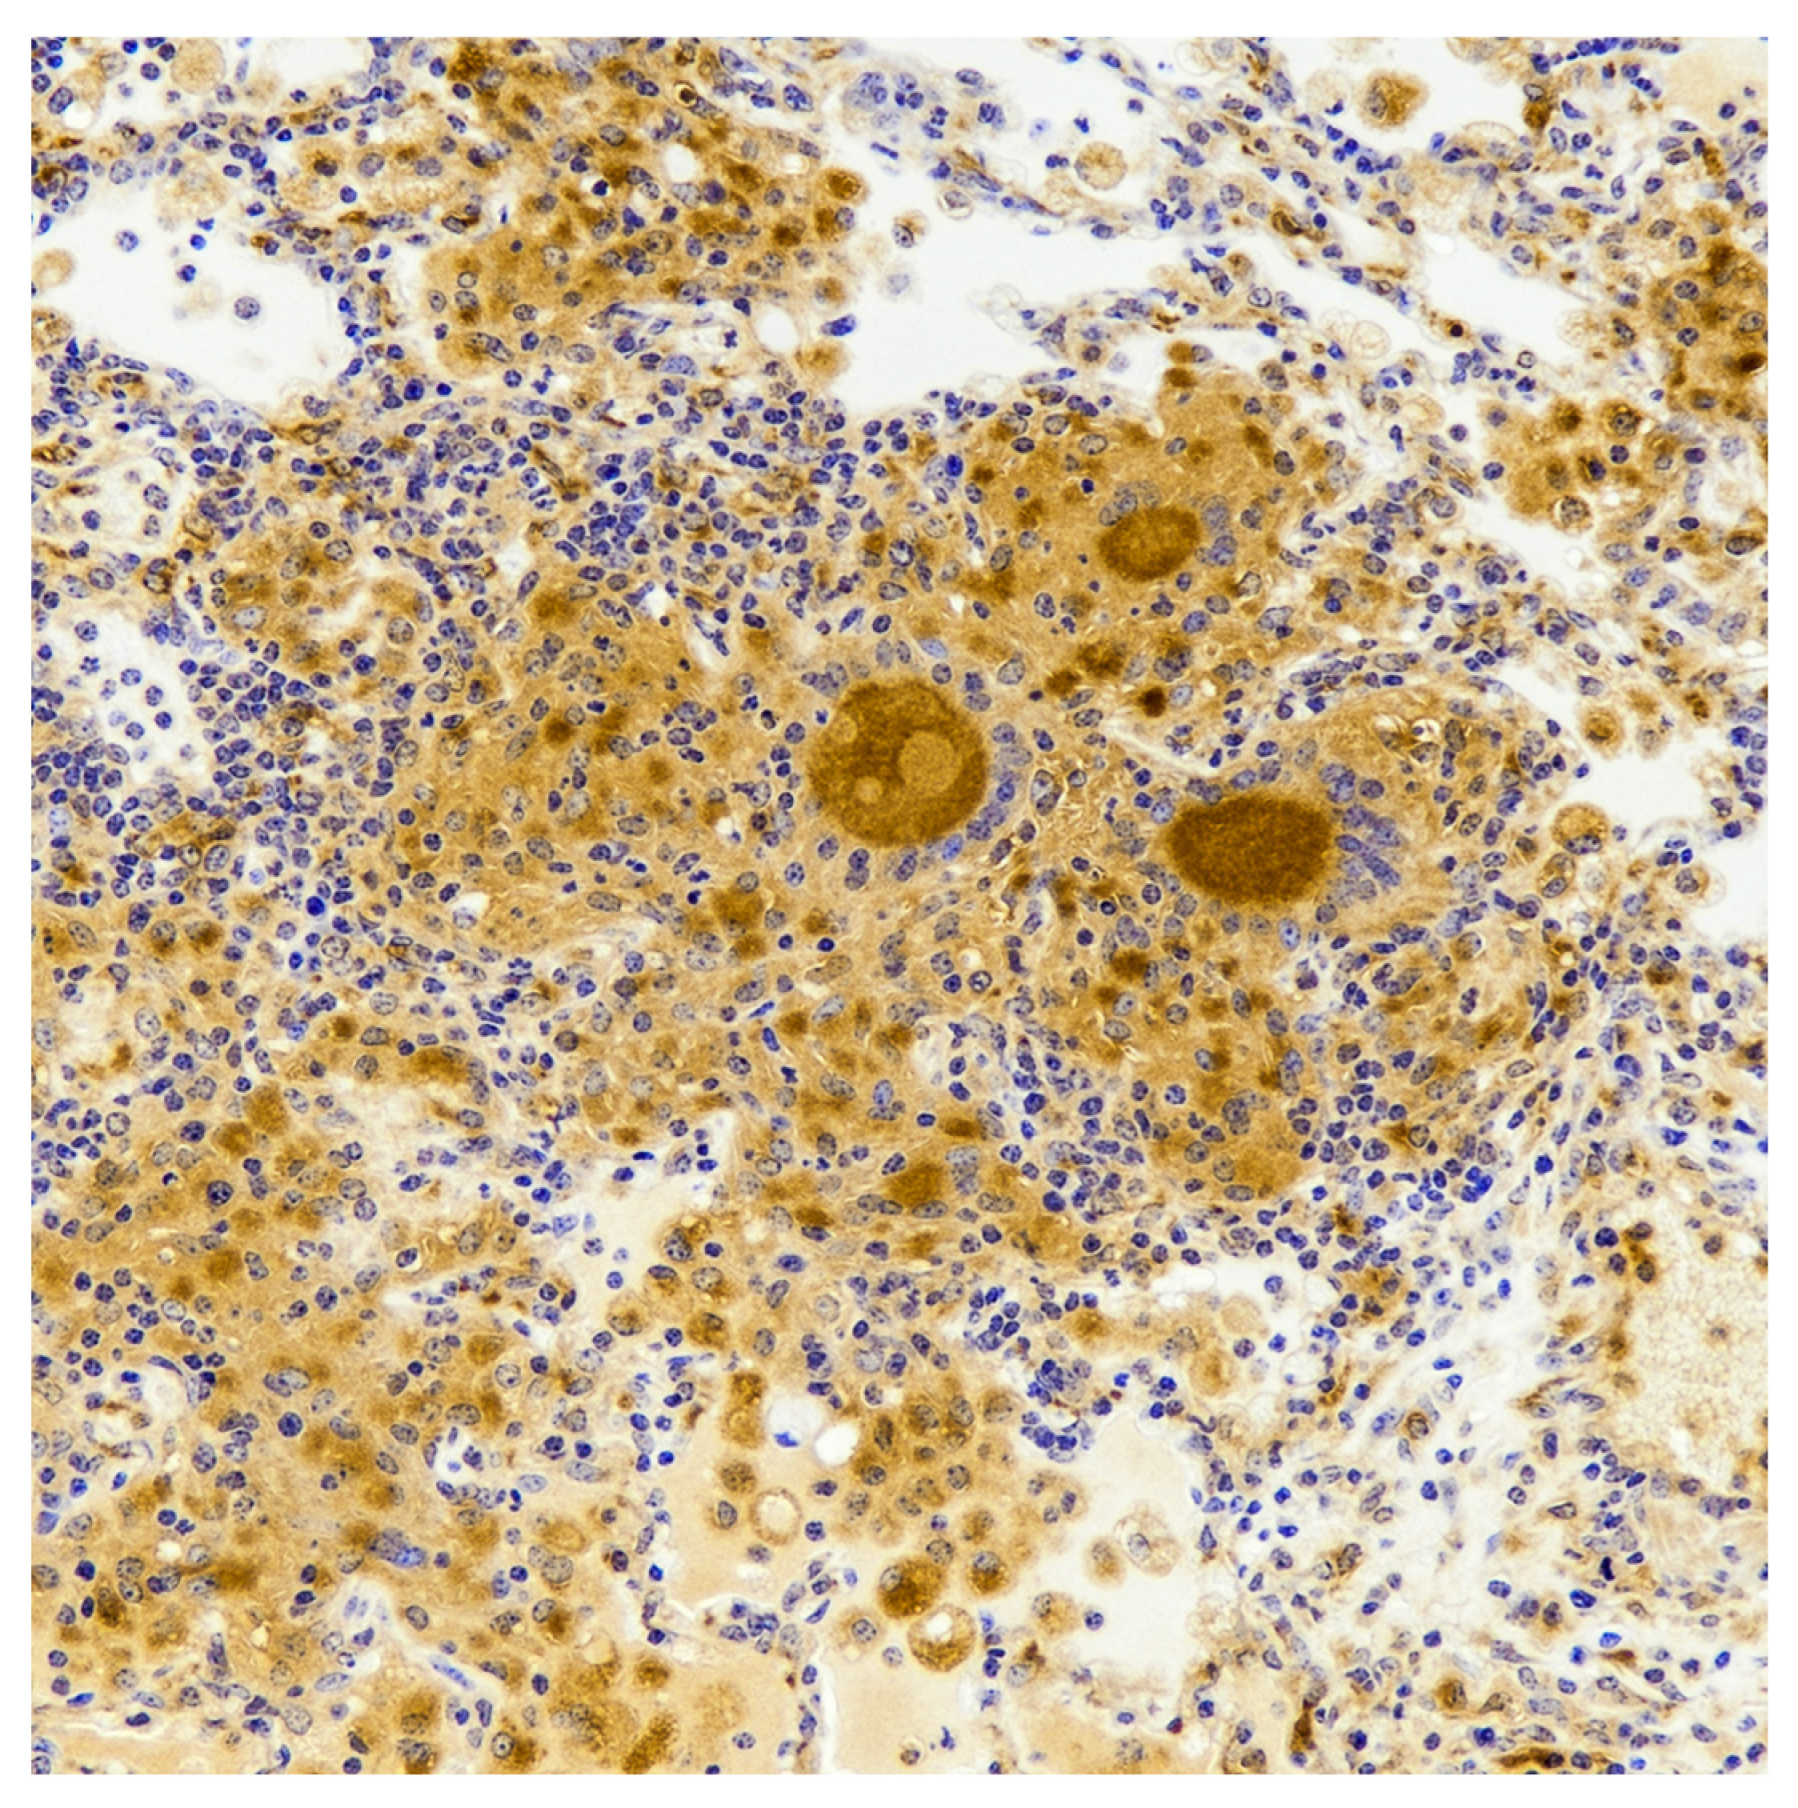

- Palmer, M.V.; Waters, W.R.; Thacker, T.C. Lesion development and immunohistochemical changes in granulomas from cattle experimentally infected with Mycobacterium bovis. Vet. Pathol. 2007, 44, 863–874. [Google Scholar] [CrossRef]

- Pereira-Suarez, A.L.; Estrada-Chavez, C.; Arriaga-Diaz, C.; Espinosa-Cueto, P.; Mancilla, R. Coexpression of NRAMP1, iNOS, and nitrotyrosine in bovine tuberculosis. Vet. Pathol. 2006, 43, 709–717. [Google Scholar] [CrossRef]

- Facchetti, F.; Vermi, W.; Fiorentini, S.; Chilosi, M.; Caruso, A.; Duse, M.; Notarangelo, L.D.; Badolato, R. Expression of inducible nitric oxide synthase in human granulomas and histiocytic reactions. Am. J. Pathol. 1999, 154, 145–152. [Google Scholar] [CrossRef]